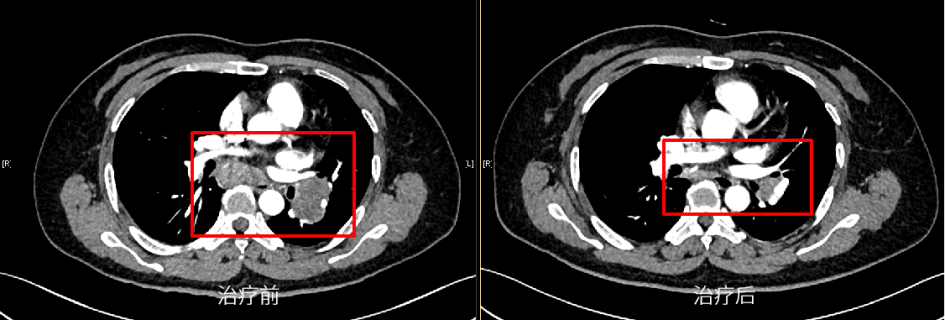

肺癌是严重威胁人民群众生命健康的恶性肿瘤,晚期肺癌患者已错失最佳手术时机,传统的化疗方案对于晚期肺癌患者的总体效果难以满足临床需求[1]。近年来,以PD-1/PD-L1抑制剂为代表的免疫疗法在肺癌治疗中的价值得到积极探索,我国自主研发的PD-1抑制剂替雷利珠单抗在肺癌领域也进行了广泛布局,目前已获批晚期非小细胞肺癌(NSCLC)一线及二/三线治疗适应症,且是唯一实现不可手术局晚及晚期NSCLC医保全程覆盖的PD-1抑制剂。 本期由中山大学孙逸仙纪念医院丁嘉萱医生为大家分享一例替雷利珠单抗用于晚期肺腺癌伴脑转移患者的诊疗过程,并由刘宜敏教授进行点评。该病例中,患者接受替雷利珠单抗治疗已实现超2年持续CR,目前免疫治疗已满两年,遂停止治疗,患者一般情况良好,后续定期影像学随访。 分享专家 丁嘉萱 医生 肿瘤学硕士 中山大学孙逸仙纪念医院放疗科医师 点评专家 刘宜敏 教授 病例详情 基本情况 一般情况:患者女性,53岁。 主诉:因“咳嗽伴气促4月,头痛半月”就诊。 现病史:患者咳嗽伴气促4月,头痛半月,于2020.05我院首诊。 既往史、个人史及家族史:无特殊。 月经婚育史:无特殊。 辅助检查 入院后基线评估: (1)胸部CT示:左肺门区可见一团块状影,大小约42.8mm*30.0mm,边界清,增强扫描呈轻度强化,强化尚均匀,病变包埋左下肺动脉,左肺下叶支气管狭窄,病变下缘可见子灶。纵隔内结构清楚,后纵隔内可见一团块状影,大小约52.8mm*21.0mm,边界清,强化方式与上述病灶相仿,与食管分界不清。双侧肺门淋巴结转移。 入院后胸部CT检查 (2)头颅MRI示:左颞叶、脑干见结节状稍长T1、稍长T2信号影,DWI呈稍高信号,增强后明显强化,周围见片状水肿影,直径分别为8.7mm和11.2mm;左颞叶、脑干异常信号灶,结合病史,考虑转移瘤;全腹MR和全身骨显像无明显异常。 入院后MRI检查 (3)超声支气管镜引导下的经支气管针吸病理活检(EBUS-TBNA):1、左上叶下舌段支气管及左下叶背段支气管,左下叶基底段支气管管腔外压性狭窄;2、隆突增宽;3、纵隔淋巴结转移(第7组,第11L组),EBUS-TBNA细胞病理提示为肺来源腺癌。 于左侧第二隆突探及第11L组淋巴结行EBUS-TBNA (4)免疫组化:TTF-1(+)、NapsinA(+)、CK7(+)、CK5/6部分(+)、Ki67约25%(+),P40(-),PD-L1(22C3)肿瘤细胞约30%(+)、PD-L1(22C3)免疫细胞约20%(+)。 (5)基因检测:RET基因重排。 临床诊断 左肺腺癌伴脑转移(T4N3M1c,IVB期);RET基因重排 诊疗经过 于2020.06.01、2020.06.22、2020.07.13、2020.08.04、2020.08.25、2020.09.15予替雷利珠单抗200mg+培美曲塞800mg+奈达铂110mg治疗6周期;期间于2020.06.04-2020.07.13行WBRT(37.5Gy/15f)+SRS(14Gy),WBRT同期给予替莫唑胺(75mg/m2)。 免疫治疗2周期后复查胸部CT提示:左肺门区肿块较前缩小(21*14mm),后纵隔淋巴结较前缩小(22mm*9mm),左颞叶病灶基本消失、脑干病灶明显缩小(5mm),水肿明显消退。疗效评估为PR。免疫治疗4周期后复查胸部CT,疗效达到CR。 治疗前vs. 免疫治疗2周期后复查胸部CT结果对比 治疗前vs. 免疫治疗2周期后复查胸部CT结果对比 治疗前vs. 免疫治疗4周期后复查胸部CT结果对比 后暂停免疫联合化疗,于2020.09.17-2020.10.30行肺癌累及野放疗(pGTV、pCTV:60Gy/30f)。后于2020.11.12-2022.08.25行替雷利珠单抗200mg+培美曲塞500mg维持治疗23周期。期间定期影像学随访(外院),疗效维持CR。 2021.11.17胸部CT提示:左肺下叶背段及左肺上叶近肺门区团片状密度增高影,其内支气管稍扩张,邻近胸膜可见增厚,同前大致相仿。右肺上叶纵隔旁至近肺门区亦见条片状实变影,部分沿支气管分布,局部支气管稍扩张;右肺中叶内侧段见少许条状影,同前大致相仿。少量心包积液较前稍增多,新见双侧胸腔少量积液。纵隔内见多枚小淋巴结。附见肝右叶后段低密度灶部分向外突出,肝脏余部另见低密度小结节,十二指肠降段见含气囊袋影,同前大致相仿。 2021.12.16头颅MRI(平扫+增强)提示:脑桥右侧区见一小条片异常信号影,T2W1及FLAIR上呈稍高信号,信号较前减低,T1W1上显示欠佳,增强扫描现片未见明确强化,余颅内脑组织形态、信号正常,中线结构居中,脑室系统形态、大小正常,脑池、脑沟及脑裂未见异常,小脑未见异常信号。增强后脑组织强化正常,未见异常信号灶。附见:双侧筛窦及右侧上颌窦黏膜少许增厚。 2022.06.23 PET-CT检查提示:1、左肺癌治疗后,左肺下叶背段及左肺上叶近肺门区斑片状密度增高影伴轻度代谢增高,病灶较前明显吸收,代谢较前减低,考虑放射性肺炎较前吸收、好转,建议追踪复查;2、左侧肺门(10L)及纵隔内(4R、5、7 组)多个小巴结,代谢未见明显增高,结合病史,考虑为淋巴结转移灶治疗后处于明显抑制状态,建议追踪复查;3、脑转移瘤治疗后,颅脑未见明显提示脑转移瘤的高代谢灶,结合病史,考虑脑转移瘤治疗后好转,请结合MRI增强结果。 患者接受免疫治疗满两年(末次治疗时间为2022.08.25),疗效维持CR,与患者充分沟通后,停止免疫维持治疗,定期随访。 2022.11.22头颅MRI(平扫+增强)提示:脑桥右侧区见一小条片异常信号影,T2W1及FLAIR上呈稍高信号,T2W1上显示欠佳,增强扫描未见明确强化,较前大致相仿。双侧顶叶及左基底节区异常信号灶。余颅内脑组织形态、信号正常,中线结构居中。脑室系统形态、大小正常,脑池、脑沟及脑裂未见异常。增强后余脑组织强化正常,未见异常信号灶。附见:双侧筛窦及上颌窦黏膜少许增厚。 2022.12.23胸部CT提示:双肺门区条片状实变影较前缩小、变淡,局部支气管通畅,增强扫描未见明确异常强化灶;右肺中叶内侧段见少许条状影,同前相仿。心包未见积液。纵隔及肺门未见肿大淋巴结;双侧胸腔未见积液。附见肝右叶后段低密度灶部分向外突出,最大横断面约4.4*2.5厘米,增强扫描呈早出晚归强化特点。肝脏余部另见低密度无强化小结节。十二指肠降段见含气囊袋影。 病程回顾 病例点评 该患者在完善相关检查后,最终被确诊为“左肺腺癌伴脑转移、后纵隔与双侧肺门淋巴结转移”。肺癌起病隐匿,约10%-25%的NSCLC患者在确诊时已发生脑转移,约50%的患者在疾病进展中发生脑转移[2]。肺腺癌作为NSCLC的主要病理类型之一,其发病率近年来持续上升[3]。 肺癌脑转移患者的死亡率很高,传统的治疗手段疗效非常有限。数据显示,在未接受治疗的脑转移患者中,中位OS仅为1个月,而接受最佳支持疗法的患者OS约为2个月[2]。近年来,免疫药物及靶向药物的研发问世,大大提高了肺癌脑转移患者的生存率。该患者PD-L1表达阳性,一项汇总分析结果显示[4],对于PD-L1 TPS≥1%的NSCLC脑转移(包括未经治)患者,相比单纯化疗,免疫治疗可改善治疗结局,同时具有更少的不良事件。 有研究表明[5],免疫联合放疗不仅可控制照射区原发肿瘤增殖,同时也能促进肿瘤组织释放抗原形成原位灭活疫苗增加免疫治疗疗效。在一项研究报道中,NSCLC脑转移患者接受免疫联合立体定向放疗安全性良好,不仅降低照射野外复发率,还可提高患者生存期[6]。此外,基因检测提示该患者存在RET基因重排,但我国首个高选择性RET抑制剂获批时间为2021年3月,在该患者2020年6月开始接受治疗时靶向药物暂不可及。 证据显示,免疫联合化疗具有协同增效作用[7],结合该病例具体情况及循证医学证据决定采用免疫联合化疗进行治疗。考虑到该患者为异地就医,为有效管理,提高患者依从性,需选择半衰期长的免疫药物,而我国自主研发的PD-1抑制剂替雷利珠单抗终末半衰期约为26天,达到同类药物最高范围,经MDT讨论予替雷利珠单抗联合化疗,并行WBRT+SRS(WBRT同期给予烷化剂)。近年来,替雷利珠单抗全面布局肺癌领域,积累了丰富的循证医学证据。 RATIONALE 304[8]为一项III期、多中心、随机、开放研究,旨在对比替雷利珠单抗联合化疗和单用化疗一线治疗晚期非鳞状NSCLC的疗效和安全性。在2022 ESMO IO大会上,RATIONALE 304研究公布了最新数据,中位随访16.1个月后,替雷利珠单抗联合化疗组的mPFS进一步延长至9.8个月,显著降低37%的疾病进展风险,ORR达到57.8%,其中CR率提升至4.9%,约为对照组的3倍;mDOR进一步提升至10.6个月,患者获益持久。同时,该研究在此次大会上首次更新了OS数据,联合治疗组的mOS达到21.6个月,HR为0.68,显著降低32%的死亡风险。此外,在RATIONALE 304研究[9]的事后分析中,首次探索了免疫治疗联合化疗的至缓解时间分布,旨在充分了解免疫治疗的反应特征、最大化免疫治疗的临床获益提供了全新思路。结果显示,替雷利珠单抗联合化疗治疗有近50%的应答者在第二次评估后(≥4周期治疗后)出现首次缓解,提示若首次肿瘤评估未达到肿瘤缓解,不必急于停药,继续治疗仍很有可能达到缓解;75%达到CR/PR的患者通过持续治疗,肿瘤会持续退缩,首次缓解到最大肿瘤缓解的中位时间为3.6个月(约5个周期),肿瘤缓解深度更深的应答者,其PFS有延长的趋势,提示已达到CR/PR的患者,持续治疗肿瘤可进一步缩小,实现更长PFS获益。 患者在接受替雷利珠单抗联合治疗2周期后快速达PR,4周期疗效达到CR。6周期后暂停免疫治疗,在针对肺癌累及野放疗后,继续予免疫联合化疗维持治疗23周期,考虑到患者耐受性,在保证疗效的基础上化疗药物(培美曲塞)由标准剂量减量至500mg,以提高生活质量,期间影像学随访疗效维持CR。该患者共接受替雷利珠单抗治疗29周期,截至发稿已实现超2年长生存,充分验证了其在真实世界中用于肺腺癌脑转移患者的有效性和安全性。 根据2020年V1版《NCCN 非小细胞肺癌临床实践指南》,如果患者一线应用免疫疗法,则应接受两年的免疫维持治疗[10],具体临床实践中免疫治疗满2年后继续用药也可持续获益。该病例中,患者自2020年6月开始免疫治疗,至2022年8月已满两年,与患者充分沟通后,停止免疫维持治疗。截至末次随访(2022年12月),患者一般情况良好,未来实现长期生存值得期待。 长期以来,生存期短、预后差的肺癌脑转移患者常被排除在临床试验之外,血脑屏障(BBB)及血液-肿瘤屏障(BTB)等特殊结构也给脑转移相关机制研究造成重重困难[2]。目前,免疫联合放疗还有许多亟待解决的问题,如疗效评价、治疗结合时机、放疗范围及剂量等[5]。期待在未来,该领域能有更深入的研究进展,造福万千肺癌脑转移患者! 参考文献: [1] 王渊, 谭盼, 等. 中国医院用药评价与分析. 2023,23(03). [2] 马力, 朱娅, 等. 中国医药导报. 2023,20(03). [3] 李芳, 韩采利, 等. 肿瘤防治研究. 2023,50(03). [4] Aaron S Mansfield, et al. JTO Clin Res Rep. 2021 Jul 1;2(8):100205. [5] 周冲, 韩亮, 等. 中华转移性肿瘤杂志,2022,05(4):340-343. [6] Kamran A Ahmed, et al. J Neurooncol. 2017 Jun;133(2):331-338. [7] 赵景景, 李玲, 等. 实用癌症杂志. 2022,37(06). [8] Shun Lu, et al. ESMO IO 2022: 138P. [9] Lu S , et al. CSCO 2022. [10] NCCN Guideline NSCLC 2020.V1.